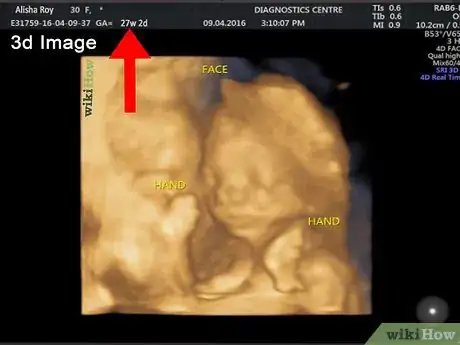

Consider a 3D or 4D ultrasound. If you are interested in seeing more details of your baby than a traditional ultrasound can provide, then you may want to ask your doctor about a 3D ultrasound. A 3D ultrasound can show your baby’s facial features and it may even be able to detect certain defects, such as a cleft lip and palate.[10] A 4D ultrasound uses the same imaging as a 3D scan, but a 4D scan makes a short video recording of your baby in the womb.[11]

• If you want to have a 3D or 4D ultrasound, the best time to do so is between 26 to 30 weeks.

• Keep in mind that these scans can be quite expensive and may not be covered by your insurance unless there is a medical reason to have one done, such as to investigate an abnormality.